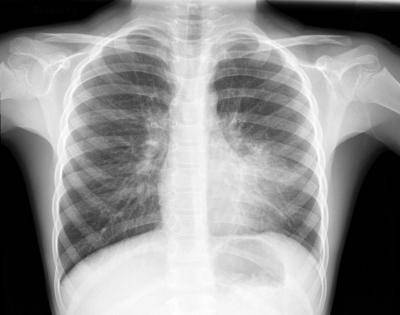

Самым результативным способом выявления болезни легких, является прослушивание новорожденного на присутствие хрипов в области грудной клетки и рентгеновское исследование.

Диагностика пневмонии у новорожденных проводиться с помощью рентгенологических и лабораторных исследований. Кроме того, верная постановка диагноза невозможна без учета клинических симптомов и данных анамнеза. Если у крохи выявлено воспаление легких, нужна госпитализация.

- Сегментарная – данный вид воспаления развивается после ОРВИ или другой вирусной инфекции. Выявить его можно только с помощью рентгеновского снимка, так как симптоматика очень незаметная и поставить диагноз на ее основании невозможно. Выздоровление, как правило, наступает на третью неделю после начала лечения.